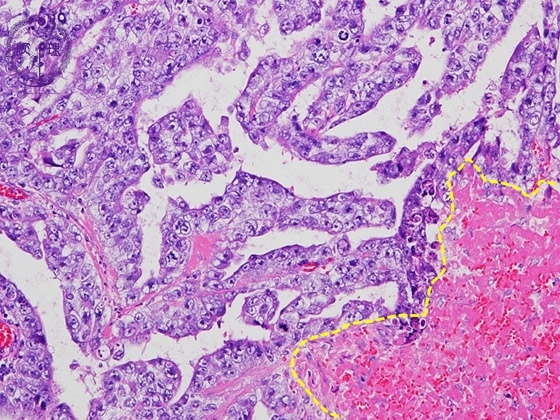

- (5)Embryonal carcinoma

Histology (HE stain, high power): Cuboidal or columnar epithelial tumor cells with severe atypia proliferate in papillary or tubular structure. Hemorrhage and necrosis are seen below yellow dotted line.